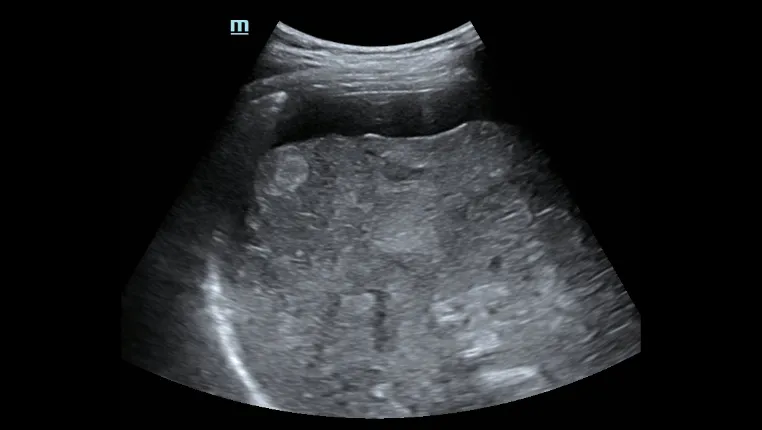

Асцит печени